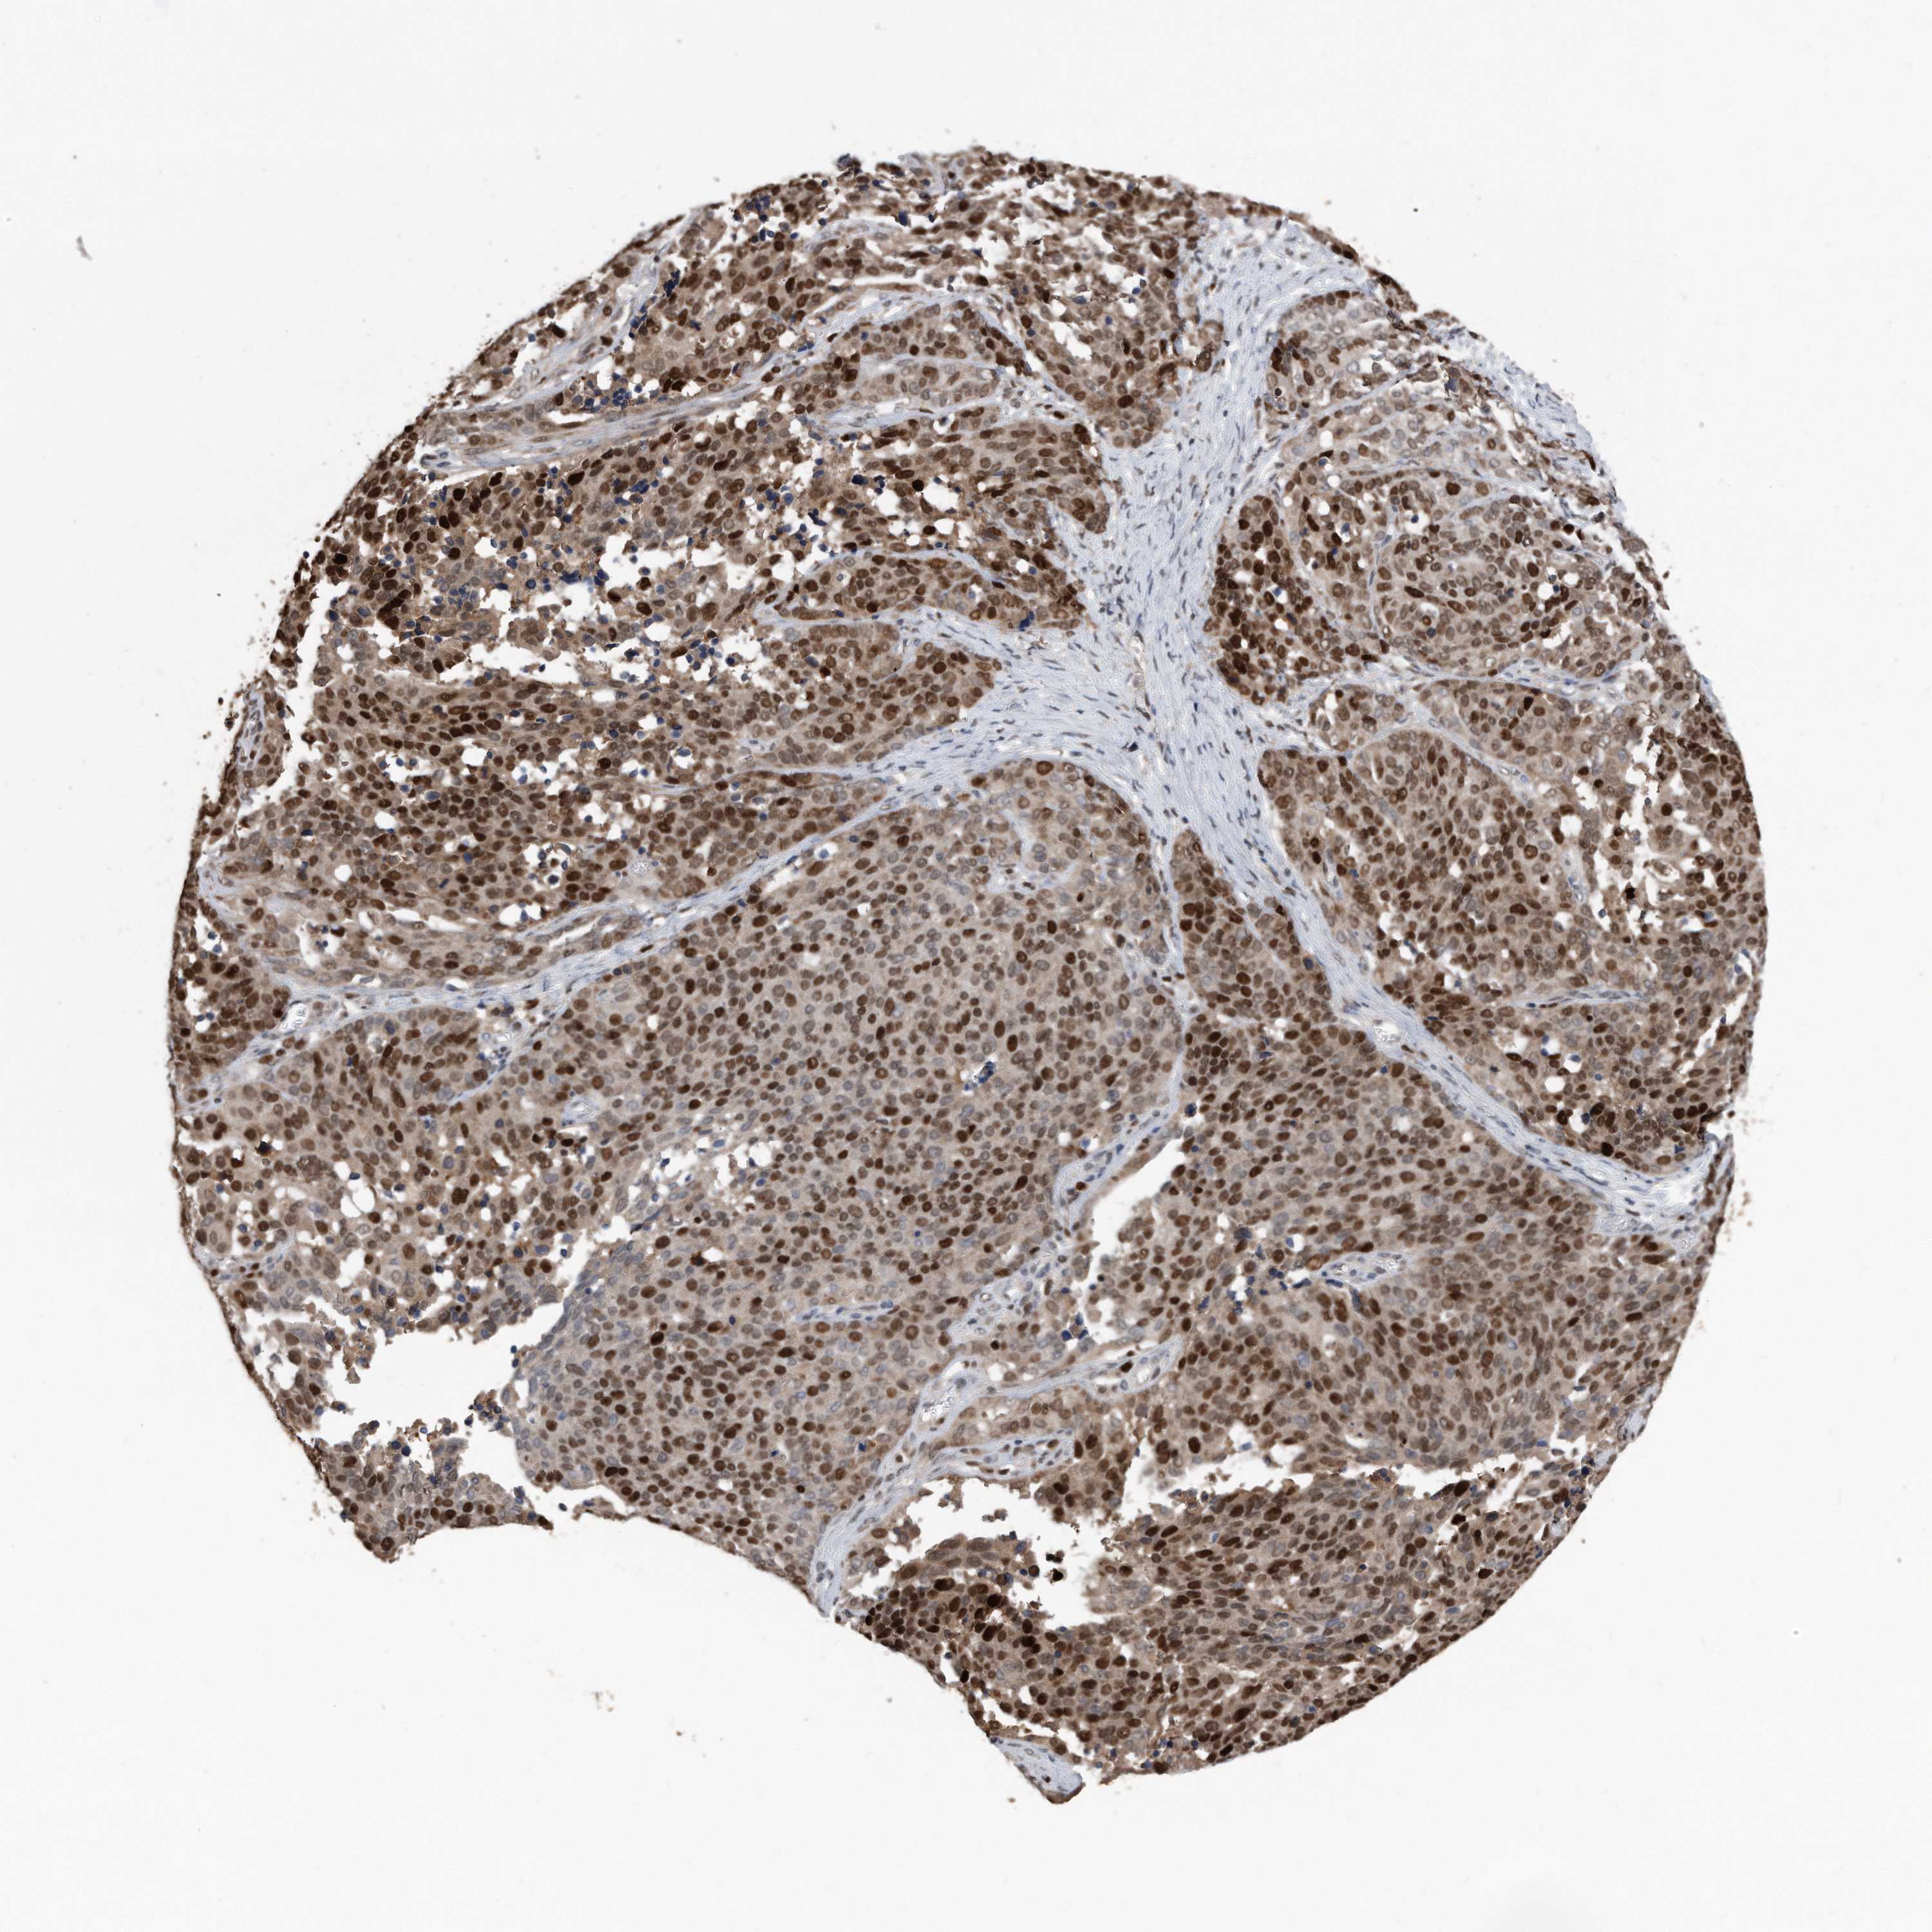

OVARIAN CANCER - Protein expressioni

A mouse-over function shows sample information and annotation data. Click on an image to view it in a full screen mode. Samples can be filtered based on level of antibody staining by selecting one or several of the following categories: high, medium, low and not detected. The assay and annotation is described here.

Note that samples used for immunohistochemistry by the Human Protein Atlas do not correspond to samples in the TCGA dataset.

Antibody stainingi

Antibody staining in the annotated cell types in the current human tissue is reported as not detected, low, medium, or high, based on conventional immunohistochemistry profiling in selected tissues. This score is based on the combination of the staining intensity and fraction of stained cells.

Each image is clickable and will lead to virtual microscopy that enables deeper exploration of all samples and also displays staining intensity scores, fraction scores and subcellular localization as well as patient and tissue information for each sample.

Cystadenocarcinoma, serous, NOS

Carcinoma, endometroid

Cystadenocarcinoma, mucinous, NOS

Carcinoma, NOS